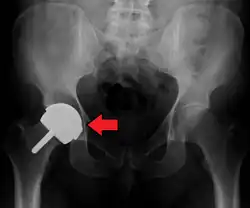

An X-ray showing a left hip (right of image) that has been replaced, with the ball of this ball-and-socket joint replaced by a metal head that is set in the femur and the socket replaced by a cup

Dislocated artificial hip

Liner wear, particularly when over 2 mm, increases the risk of dislocation.[15] Liner creep, on the other hand, is normal remoulding.[16]

Dislocation (the ball coming out of the socket) is one of the most common complications. Hip prosthesis dislocation mostly occurs in the first three months after insertion, mainly because of incomplete scar formation and relaxed soft tissues.[15] The chance of this is diminished if less tissue is cut, if the cut tissue is repaired and if large diameter head balls are used.[17] Surgeons who perform more operations tend to have fewer dislocations. Important factors which are related to dislocation are: component positioning, preservation of the gluteal muscles and restoration of leg length and femoral offset.[18] Keeping the leg out of certain positions during the first few months after surgery further reduces risk.